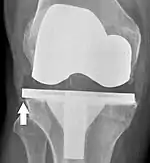

Loosening of the prosthesis can be indicated on X-ray by thin radiolucent spaces around the implant, or more obviously by implant displacement.[56]

Knee replacement is routinely evaluated by X-ray, including the following measures:

- FFC: frontal femoral component angle. It is typically regarded as optimal when being 2–7° in valgus.[63]

- FTC: frontal tibial component angle, which is regarded as optimal when being at a right angle. A varus position of more than 3° has generally been found to increase the failure rate of the prosthesis.[63]

- Anterior femoral notching (the femoral component causing reduced thickness of the distal femur anteriorly), seems to cause an increased risk of fractures when exceeding about 3 mm.[64]

- LTC: lateral (or sagittal) tibial component angle, which is ideally positioned so that the tibia is 0–7° flexed compared to at a right angle with the tibial plate.[63]